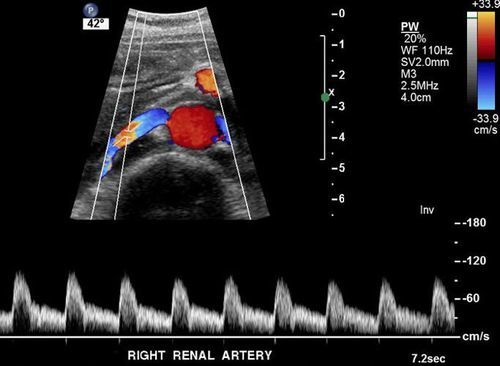

RENAL ARTER RENKLİ DOPPLER ULTRASON

Renal arter renkli doppler ultrason ile bu atardamarlardaki problemler kolaylıkla görülebilir. Eğer hipertansiyon sebebi bulunabilirse tedavi edilir ve hastanın kronik ilaç kullanması gerekmeden hipertansiyon tedavi edilir.